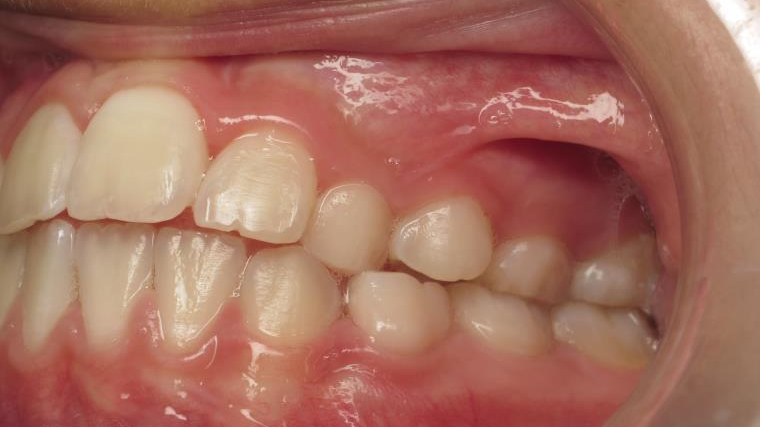

inversion des dents posterieur cote gauche

appareillage mobile pendant 9 mois